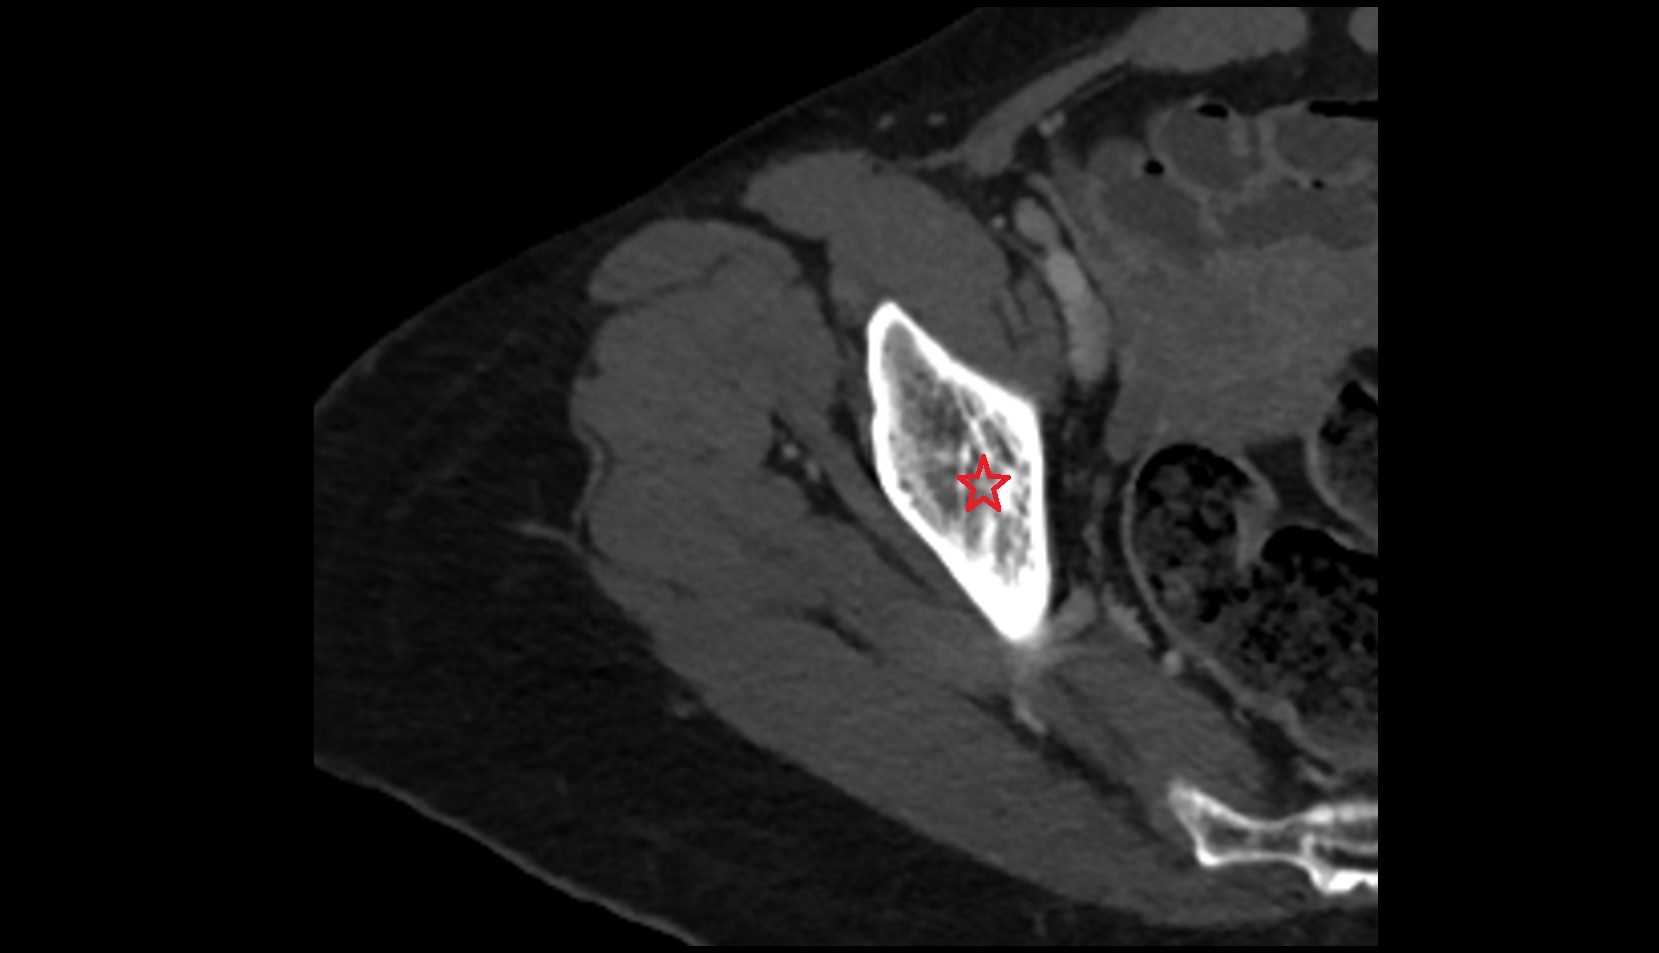

- Head of femur

- Neck of femur

- Hip joint